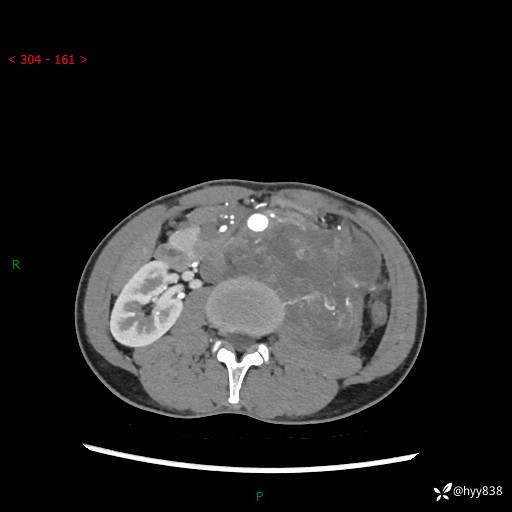

简要病史:患者无明显诱因出现左侧下腹及左侧腰背部疼痛,为间歇性隐痛,我院行胃肠镜检查,提示慢性非萎缩性胃炎,予以口服药物治疗,效果欠佳,后仍觉腹痛不适,遂至当地中医医院就诊,行彩超提示左肾积水及左肾实质性占位,遂来我院泌尿外科就诊

腹部CT平扫+增强